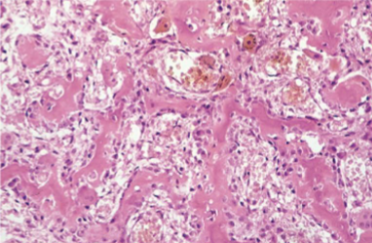

Osteosarcoma Morphology

Formation of osteoid matrix or mineralized bone (fine or lace-like pattern or broad sheets of trabeculae) by malignant pleomorphic (large hyperchromatic nuclei, bizarre giant cells) tumor cells (osteoblasts) with abundant mitosis